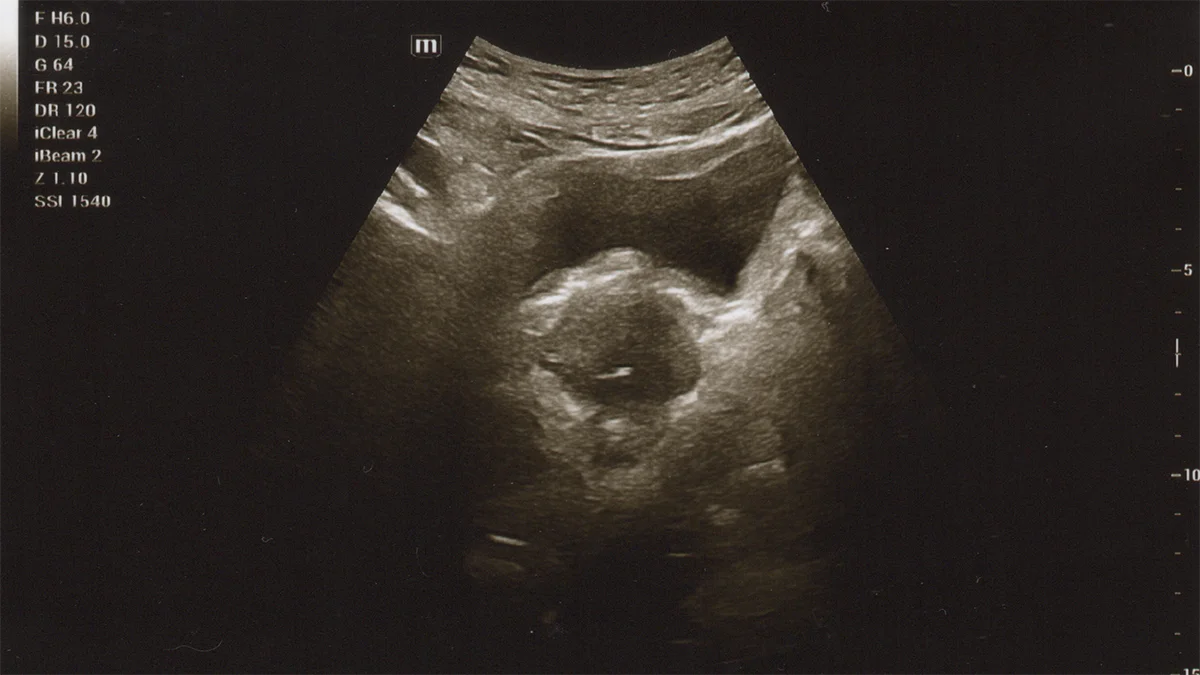

Nak… di awal catatan ini adalah foto pertamamu. Ketika pertama kali kami melihatmu yang masih berada dalam rahim ibumu. Ia adalah seorang perempuan yang kelak akan kau panggil Mama. Seseorang yang harus kau hormati dan sayangi jauh lebih hebat daripada terhadapku, yang aku ingin kau memanggilku Abah.

Benar sekali jika kelak kau berpikir bahwa cerita ini adalah tentang bagaimana kami, yang kuingin kau sebut sebagai Abah dan Mama, pertama kali mengetahui bahwa kelak dalam waktu berbulan mendatang, kau akan lahir dan hadir ke dunia ini. Lalu akan ada di tengah-tengah kami semua. Sungguh kami menantikan hari itu, bersama doa-doa.